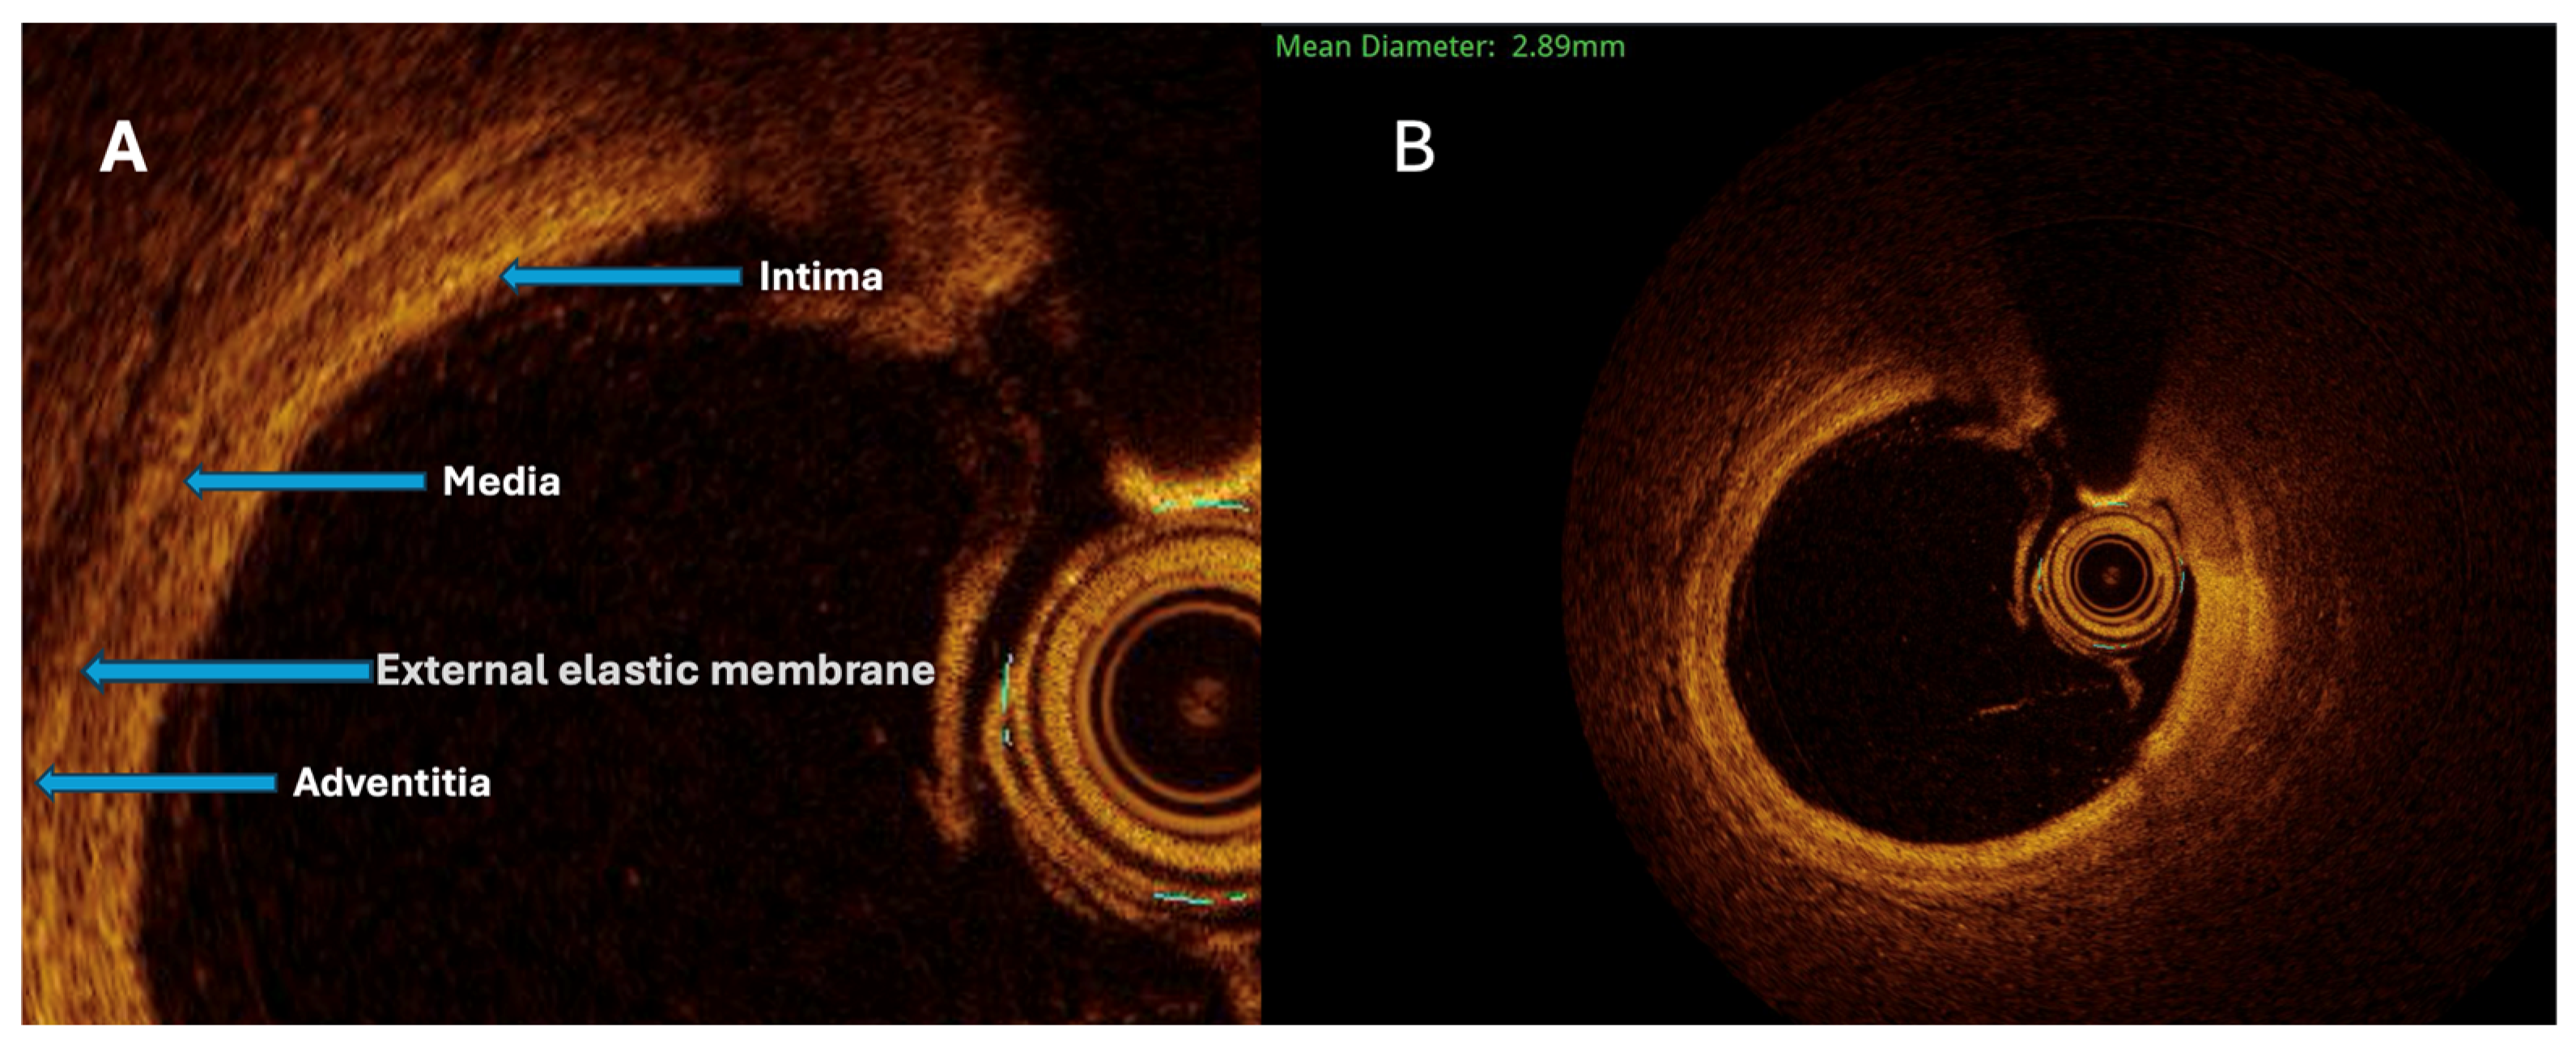

The maximal aneurysm diameter (right, within the aneurysmal segment) is measured perpendicularly across the lumen at the point of most significant dilation. The reference diameter (left) is measured perpendicularly across the lumen of the adjacent, non-dilated (normal) segment of the same vessel, proximal to the aneurysm. The aneurysmal ratio is calculated as the maximal aneurysm diameter divided by the reference diameter; values ≥1.5 indicate aneurysmal remodeling according to standard interventional definitions. The normal coronary vessel, with all its layers, is presented in

Figure 3.

Both quantitative and qualitative OCT analysis assessed vascular remodeling. Quantitative assessment included measurements of intimal and medial thickness, as well as the calculation of the intima-to-media thickness ratio. Qualitative evaluation was based on the identification of specific morphological features, including fibrosis, calcification, cellular infiltration, neovascularization, and thrombus formation. Homogeneous areas with strong backscattering and mild signal attenuation characterized fibrosis. Calcifications were defined as well-demarcated regions with low signal intensity and minimal attenuation. Cellular infiltration was identified as signal-rich bands with strong light attenuation resulting in shadowing. Neovascularization appeared as ellipsoidal, low-signal structures consistent with microvessels (